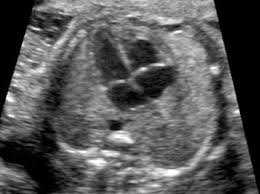

En la figura 2 se muestra la imagen ultrasonográfica del embrión a las 39,5 semanas, que muestra disminución del tamaño de la lesión pulmonar.

Figura 2. Ultrasonografía a las 38,5 semanas. Se observa disminución franca de la masa en pulmón derecho.